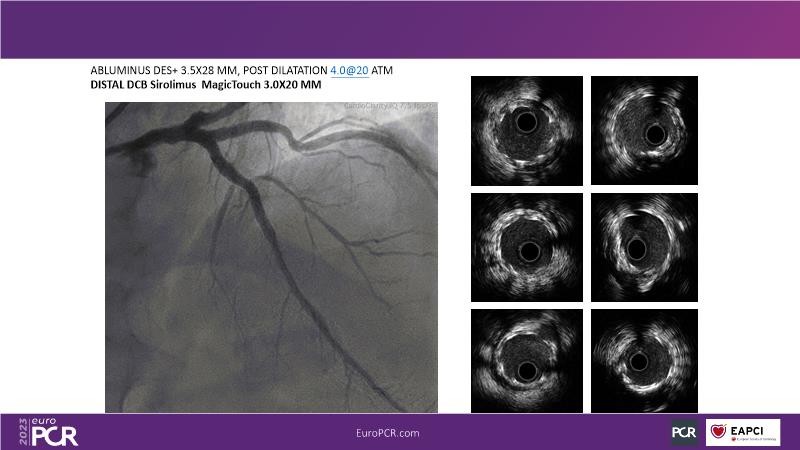

• To know why and how a fusion coating of DES+DCB stent platform is effective for the treatment of cardiovascular disease in diabetes mellitus patients via case presentations

• To understand why you can count on customised drug delivery platform of DES+DCB in complex settings with imaging-based evidence through case presentations